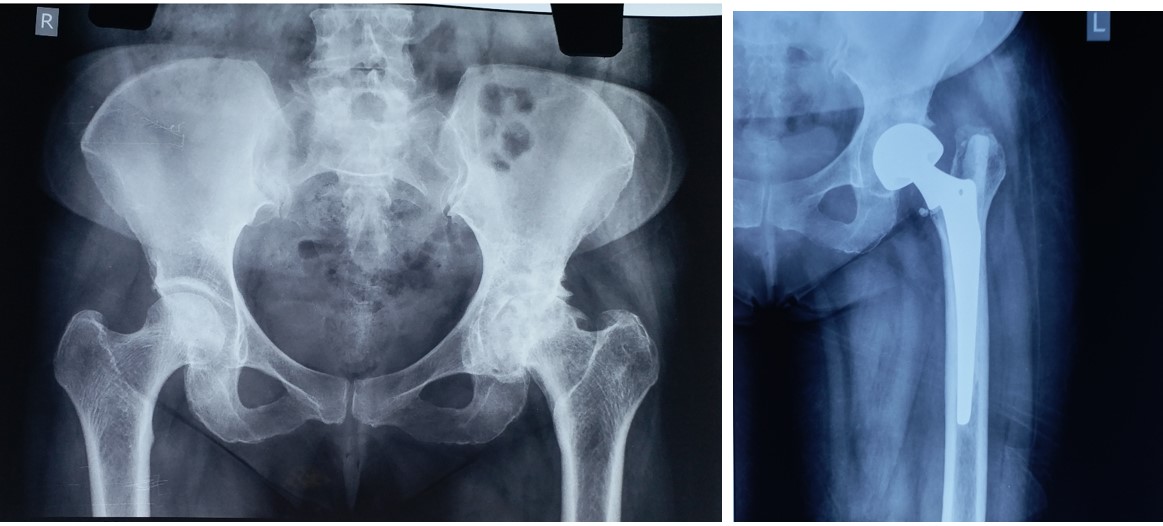

CRPP ( Closed Reduction Percutaneous Pinning )

• Most of the metaphyseal fractures of both upper and lower limbs can be successfully treated by CRPP.

• CRPP can be added to CRPIMN (Closed Reduction Percutaneous Intra Medullary Nailing) in  adult diaphyseal fractures including Monteggia and Galeazzi fractures